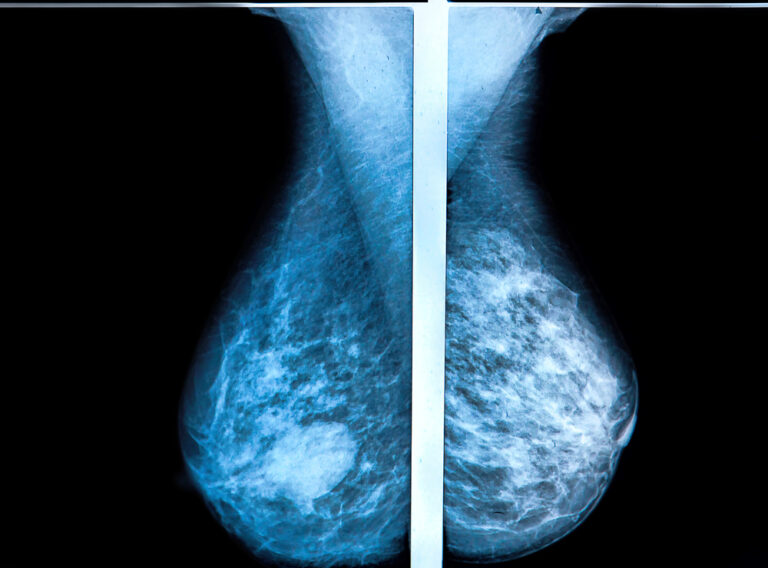

What Does High Density Breasts Mean Factors associated with higher breast density include using menopausal hormone therapy and having a low body mass index. The breasts are extremely dense (about 10% of women). If a recent mammogram showed you have dense breast tissue, you may wonder what this means for your health. When there’s more glandular and fibrous tissue than fatty tissue, your breast is considered dense. Women in the second two categories are said. Breast tissue is composed of milk glands, milk ducts and supportive tissue. It’s a normal and common finding. The breasts have almost no fatty tissue. Breasts are made up of a combination of three types of. Factors associated with higher breast density include using menopausal hormone therapy and having a low body mass index. [show] what is dense breast tissue? It does not refer to how the breast tissue feels on exam. To understand what “dense breasts” means, it helps to know a bit about breast tissue. Dense breast tissue refers to the appearance of breast tissue on a mammogram. Breast density is a measure of how much fibrous and glandular tissue (also known as fibroglandular tissue) there is in your breast, as compared to fat. Factors associated with lower breast density.

Mammogram Density What Does High Density Breasts Mean These make up the dense tissue in the breast. Breast density is a measure of how much fibrous and glandular tissue (also known as fibroglandular tissue) there is in your breast, as compared to fat. Dense breast tissue refers to the appearance of breast tissue on a mammogram. [show] what is dense breast tissue? Factors associated with higher breast density. What Does High Density Breasts Mean.